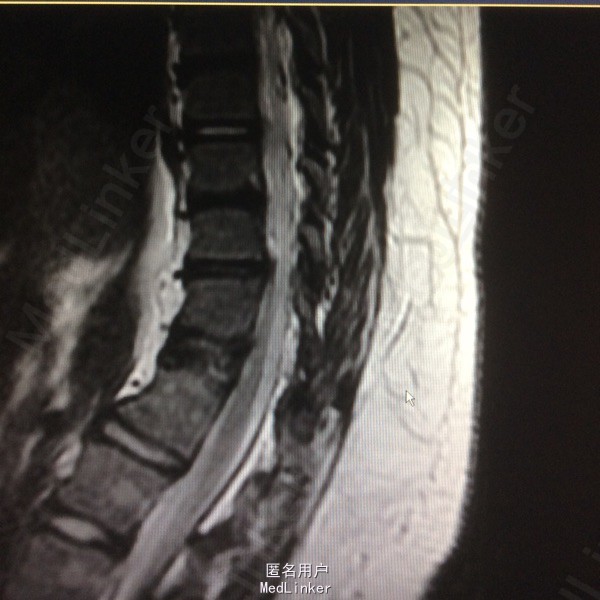

患者呈向心性肥胖,眼角略上斜,下颌小,上下牙间距大,闭齿音发音不清,性早熟,外阴幼稚,大小阴唇发育不良,手脚小胖,指端纤细,余查体无明显异常。 辅助检查:胸9-10胸12-腰1椎体融合、胸11呈半椎体,椎管内脊髓未见明显信号异常.

胸椎半椎体畸形 左侧第10肋骨缺如 隐形骶椎裂 双下肢膝外翻 双下肢肌挛缩症 脊柱畸形术,胸5、6、8、9腰1-2-3双侧椎弓根螺钉,去除胸11-12后方椎板,胸12半椎体及上下间隙间盘去除,椎间隙植骨。

本患者后凸可能是由于机制未明的神经肌肉病变,也可能是脊柱矢状位失平衡结果,若是前者导致可能会出现屈伸脊柱的平衡肌群肌张力或肌力增强或减弱,使融合后上下端再次出现冠状面或矢状面失平衡,需再次手术治疗,密切随访患者病情。